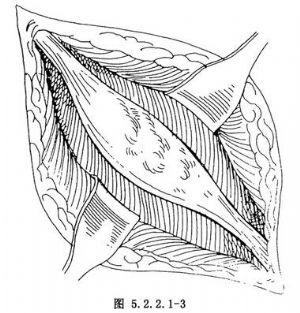

(2)顯露腫瘤:良性腫瘤處的肌層未受侵犯時,將正常的肌層向兩側遊離開,顯露出腫瘤(圖5.2.2.1-3)。